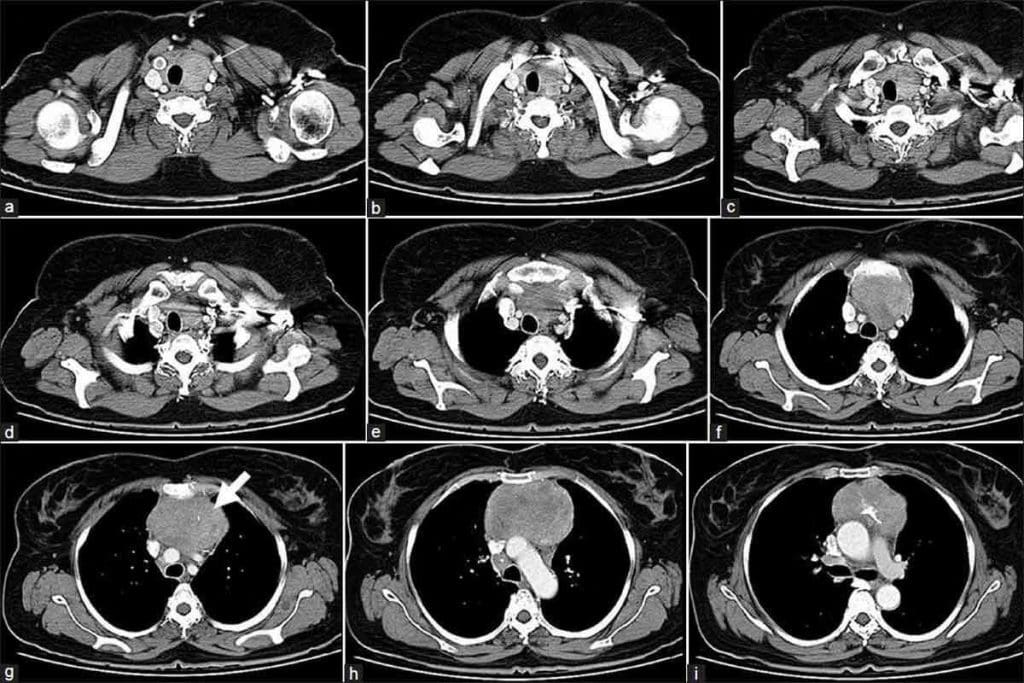

Can CT Scan Show Infection? Detecting Respiratory Conditions

Can CT Scan Show Infection? Crucial Facts on Detection

Can CT Scan Show Infection? Crucial Facts on Detection 6

CT scans are key in modern medicine for showing infections and detecting respiratory conditions. They give us detailed lung images. This helps us diagnose and manage respiratory infections well.

Identifying Pneumonia and Other Lung Infections

Diagnosing pneumonia and other lung infections can be tough with old imaging methods. But, CT scans give a full view of the lungs. This lets us spot infection areas and see how severe it is.

Key features visible on a CT scan for pneumonia include:

• Consolidation areas in the lungs

• Presence of ground-glass opacities

• Pleural effusion

Visualization of COVID-19 Related Lung Changes

COVID-19 has shown us how vital CT scans are for respiratory infections. They help us see lung changes from COVID-19. This lets us know how serious the disease is and how it’s progressing.

CT scans give us detailed lung images. This helps doctors make better decisions for patient care. We can see how much of the lung is affected and track changes. This is key for managing COVID-19 and other respiratory infections.